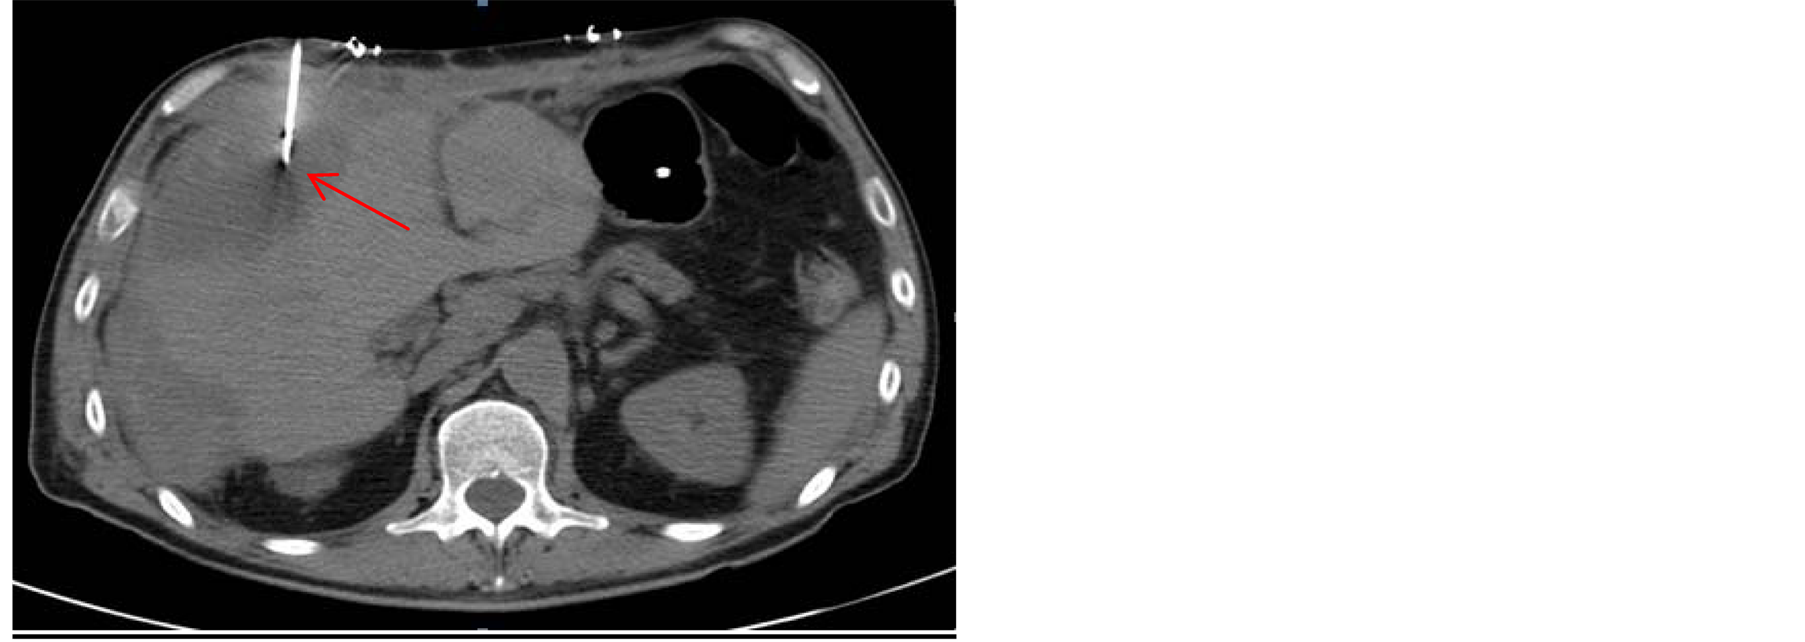

instability, selective embolization of right hepatic artery was performed, without any clear radiological improvement. Owing to further clinical deterioration, urgent surgical evacuation of the hematoma had to be undertaken 72 hours after the ERCP. In the postoperative period the patient presented infection of the collection, which indicated colocation of percutaneous drainage (Figure 3), and broad-spectrum intravenous antibiotics were administered over a period of six weeks. The patient gradually recovered and complete resolution of hematoma was seen in control CT scan, it being thus possible to withdraw the drainage catheter (Figure 4). He was discharged two months after admission in good condition.

Figure 3. Colocation of percutaneous drainage guided by abdominal CT scan.